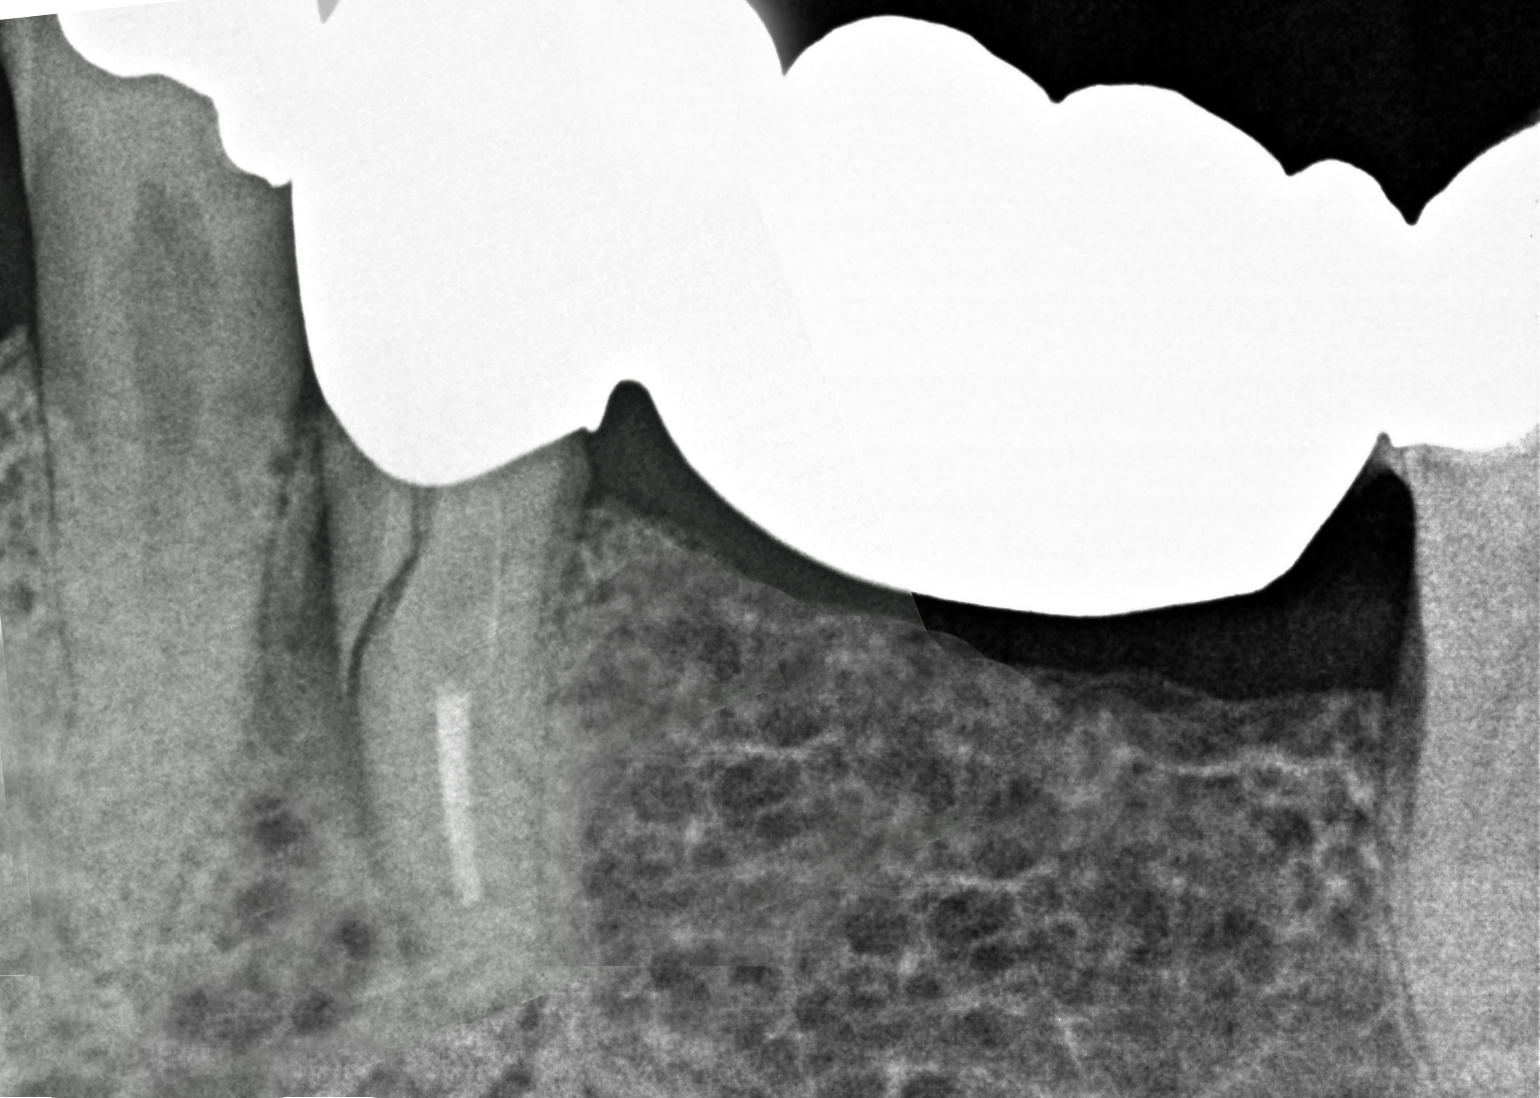

Il paziente si presenta alla nostra osservazione con l’elemento dentale 4.5 fratturato in senso verticale.

La situazione clinica appare essere la seguente: 4.5 elemento di ponte protesico con 4.6 in estensione, presenza di fistola vestibolare, sondaggio di 7 mm mesiale a radice di 4.5 fratturata con fuoriuscita ematica e purulenta (Figure 3-4).

Si effettua un bone mapping con la sonda parodontale per valutare la perdita di sostanza ossea della parete vestibolare. L’entità del difetto osseo è di circa 8 mm in senso corono-apicale per 5 mm in senso mesio-distale.

In caso di frattura radicolare verticale è frequente il riscontro di deficit osseo della parete alveolare vestibolare causato dal biofilm batterico presente nella discontinuità radicolare.